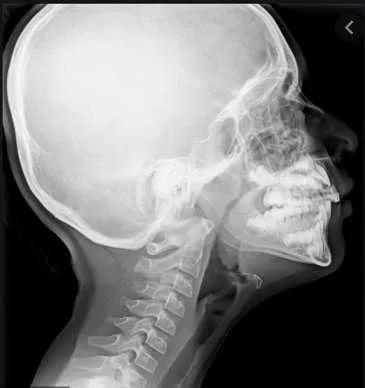

Epiglottitis

A 2-year-old unvaccinated child presented with a 6-hour history of high-grade fever, drooling, and odynophagia. The child appeared ill and irritable with inspiratory stridor. - Diagnosis: Epiglottitis. - Characteristic Sign on Neck X-ray: Thumb sign.

- : A 5-year-old child presented with fever and respiratory distress.

- Diagnosis: Acute epiglottitis.

- Management:

- Dont Examine the child in the OR.

- Intubation.

- IV antibiotics.

- Corticosteroids.

- Sign on X-ray: Thumbprint sign.

Vocal Nodules